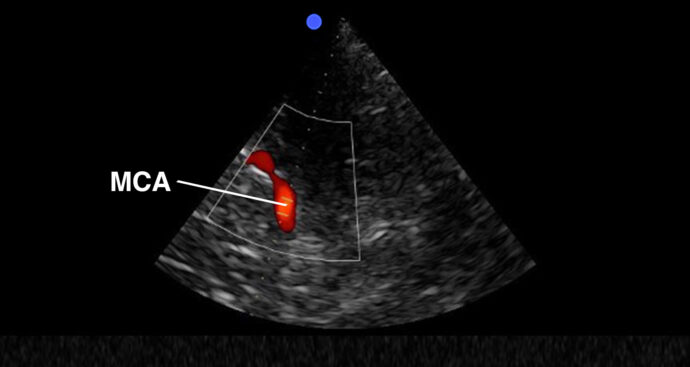

Learn to assess different organ systems such as the heart, lungs, abdomen, and vessels using POCUS

Cardiac